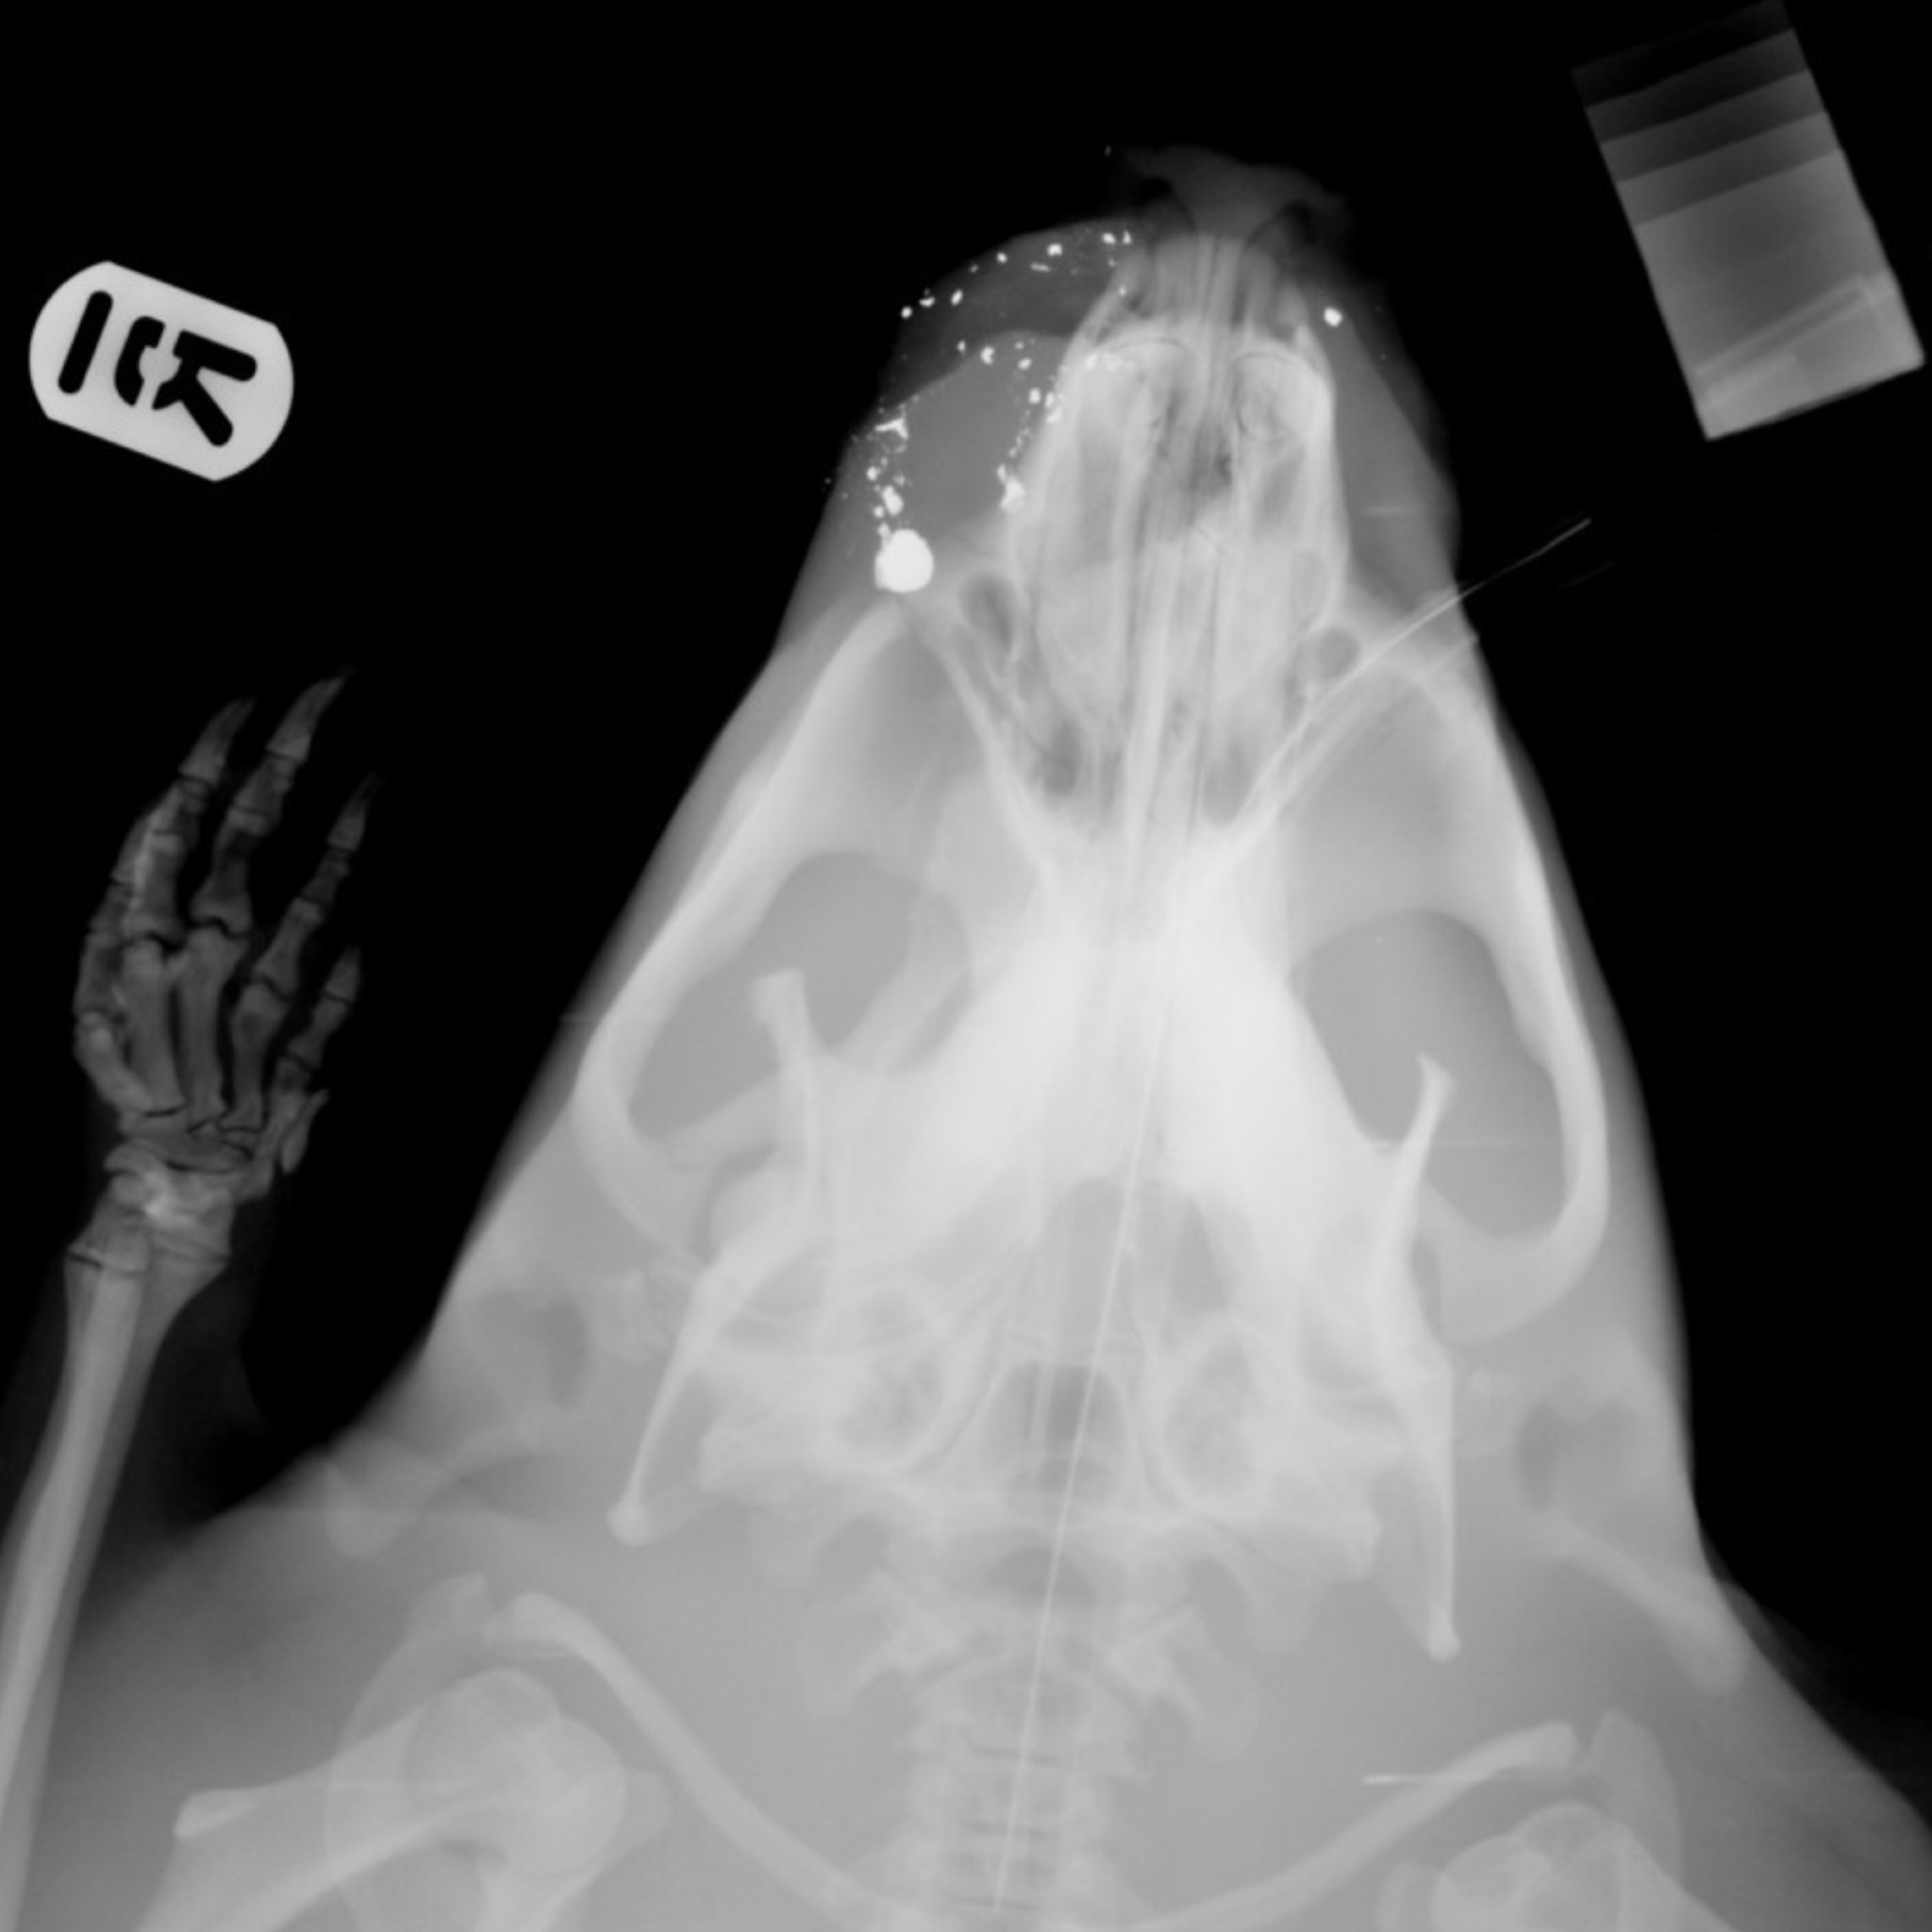

Fig was discovered by a member of the public with wounds to his face, two missing incisors and peppered with shrapnel.